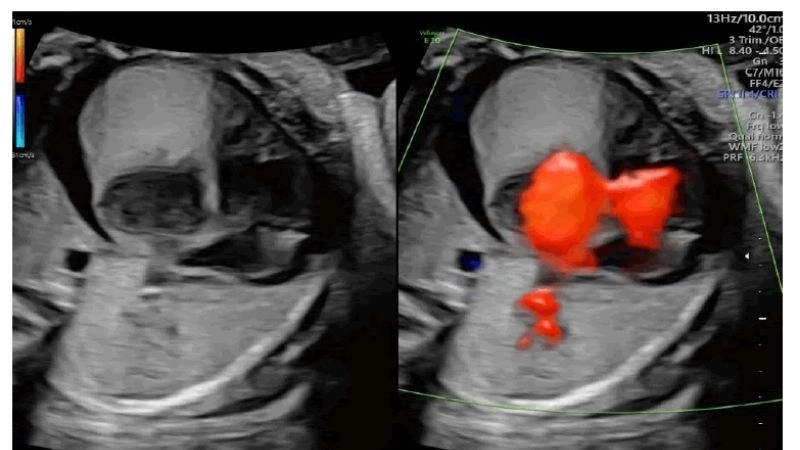

Rhabdomyoma is a rare benign tumor of striated muscle, commonly affecting the heart in children. Images often highlight cardiac masses that disrupt heart rhythm and function.

Insightful capture of fetal rhabdomyoma findings

Fascinating process of rhabdomyoma regression